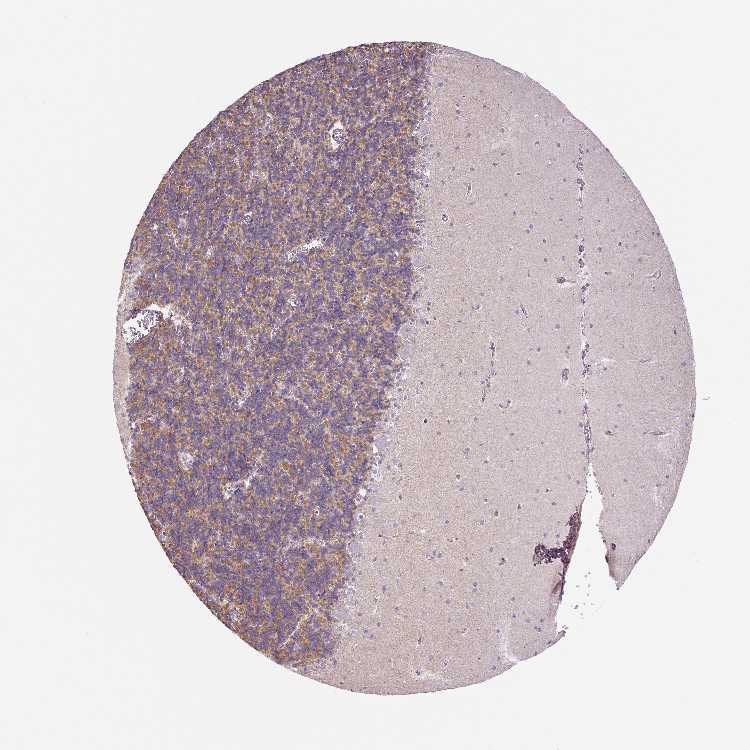

CEREBELLUM - Antibody stainingi

Antibody staining in the annotated cell types in the current human tissue is reported as not detected, low, medium, or high, based on conventional immunohistochemistry profiling in selected tissues. This score is based on the combination of the staining intensity and fraction of stained cells.

Each image is clickable and will lead to virtual microscopy that enables deeper exploration of all samples and also displays staining intensity scores, fraction scores and subcellular localization as well as patient and tissue information for each sample.

Antibody HPA055463

Purkinje cells Not detected

Cells in granular layer Medium

Cells in molecular layer Not detected